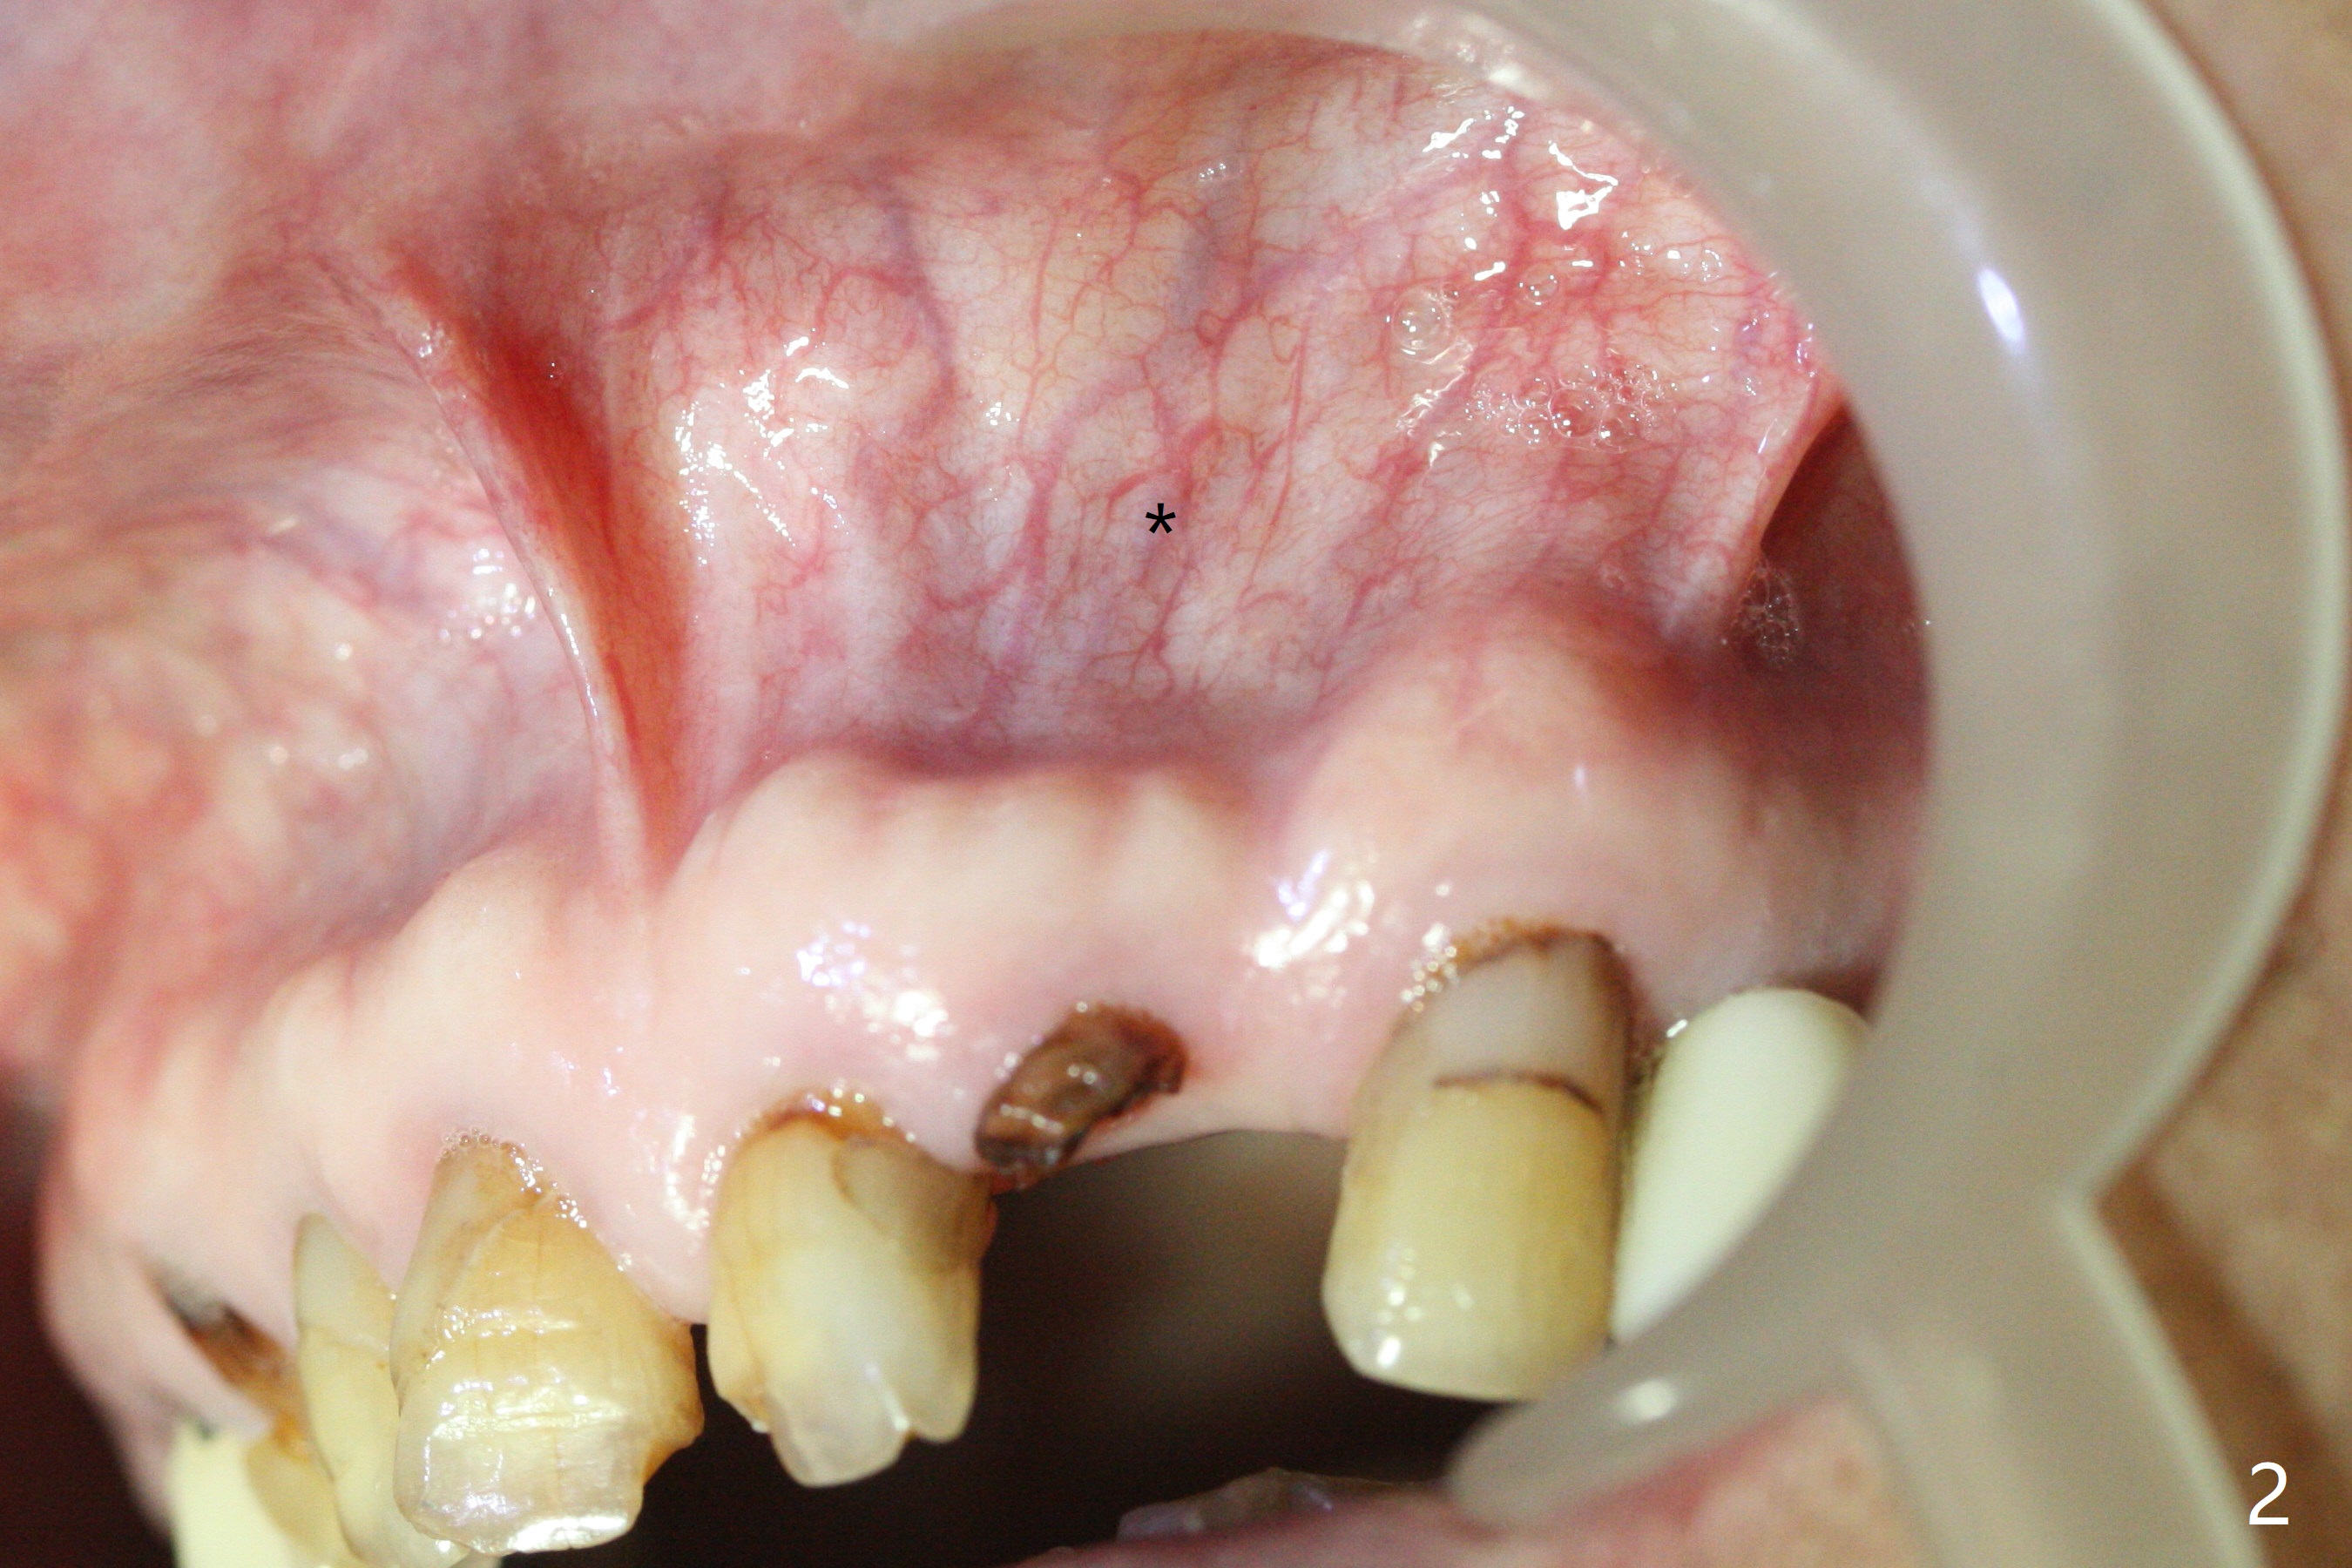

2.5 mm

A 88-year-old man fractures the upper lateral incisor (microdontia) (Fig.1). Because of the labial concavity (white dashed line), it appears that an implant smaller than 3.5 mm is appropriate for the site. Clinical examination and CBCT confirm the concavity (Fig.2,4 *). Since the tooth deviates mesial, osteotomy should be initiated distopalatal (Fig.1,4).